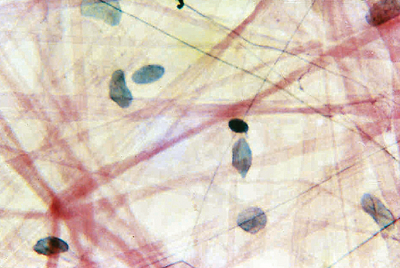

Areolar Tissue (Mammalian) Wm ,Each

AREOLAR TISSUE (MAMMALIAN) WM